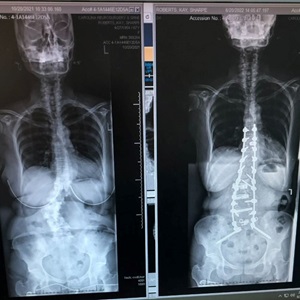

After reviewing her imaging studies, Kim determined that Kay’s lumbar spine condition had deteriorated to the point where minimally invasive surgery wasn’t a viable option and a more extensive spinal procedure would be necessary.

Kim performed an extensive reconstructive spine fusion that consisted of two stages:

- Stage I was a lateral approach with interbody fusion to help with deformity correction. This type of approach has been made possible by recent technological advances and gives the surgeon the ability to do surgery from the side rather than the front or the back, which can be much less invasive for the patient.

- Stage II provided a multilevel lumbar decompression and instrumental fusion, which helped to correct her scoliosis, a sideways curvature of the spine and straighten her spine to ensure optimal alignment.